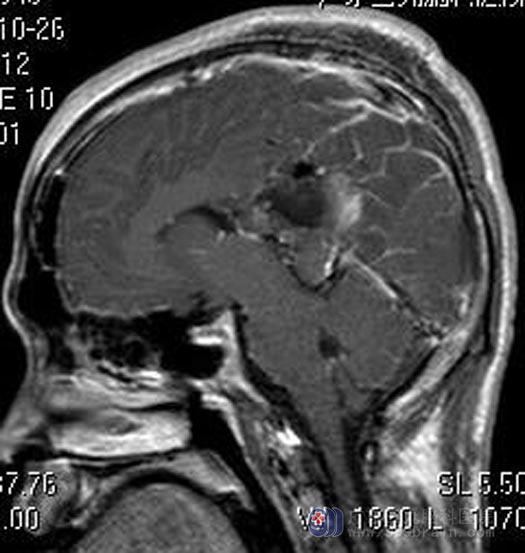

为明确病理及治疗,家属要求手术。综合神经外科鲁明主任主刀,在全麻唤醒麻醉下行左侧丘脑-扣带回-侧脑室区占位病变切除术,术前导航定位,唤醒患者,再次导航定位,电生理检查辅助,显微镜下见肿瘤呈黄褐色,胶冻样,肿瘤荧光染色,镜下分块全切除,患者功能保护完好。术后小林呕吐症状消失,康复出院。病理结果提示:血管周细胞瘤。